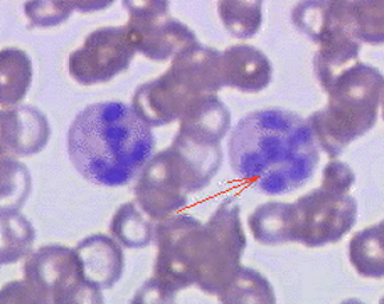

Con tali dati si eseguono ulteriori esami come dosaggio della vitamina B12 e acido folico e, nel frattempo, per escludere patologia linfoproliferativa, viene effettuata valutazione midollare che non mostra aspetti atipici ma solo granulociti ipersegmentati (Figura 1).